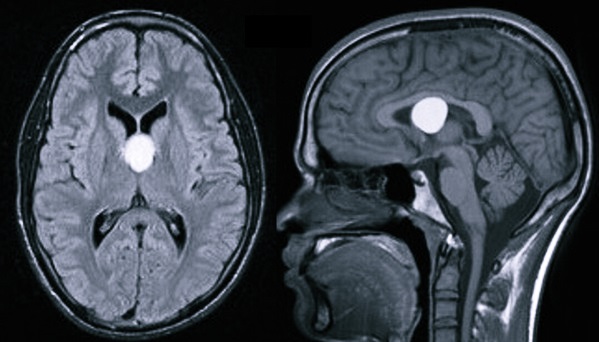

Киста в головном мозге – это объемное доброкачественное образование внутри черепной коробки, которое имеет вид полости, заполненной жидкостью. Нередко оно имеет скрытое субклиническое течение, не сопровождающееся постепенным увеличением габаритов. В основном подозрение на появление кисты внутри головы возникает, если человек страдает эпилептическими пароксизмами либо внутричерепной гипертензией. Одной из особенностей данного заболевания головного мозга является то, что у значительной доли пациентов проявляются симптомы, соответствующие очагу образования кисты – это означает, что для диагностики достаточно всего лишь КТ и МРТ, а также нейросонографии для обследования новорожденного младенца или уже подросшего ребенка.

На сегодняшний день основными методами диагностики и последующего прогноза данной болезни являются МРТ (магнитно-резонансная томография) и КТ. Полученная томограмма показывает состояние всех составляющих мозга (эпифиза, мозжечка, гипофиза, нервных ганглий и других частей). С ее помощью можно увидеть место расположения перивентрикулярного глиозного очага и атрофических рубцовых следов внутри головного мозга без вскрытия черепной коробки, оценить их форму, размеры и интраселлярный рост.

Кроме того, данные способы обследования позволяют сделать дифференциальную диагностику промежуточного состояния между доброкачественной кистой и злокачественной опухолью. После внутривенного введения специального контрастного вещества его продукт накапливается в опухолевых тканях, а киста при этом не становится контрастной.

Самым эффективным методом диагностики образований в голове является компьютерная и магнитно-резонансная томографии. С их помощью возможно увидеть четкие очертания опухоли, оценить ее размеры и степень оказываемого влияния на близлежащие ткани. Во время проведения МРТ пациенту вводится специальный контраст, который помогает определить характер образования (доброкачественный или злокачественный). Для прослеживания динамики развития опухоли МРТ проводится несколько раз.